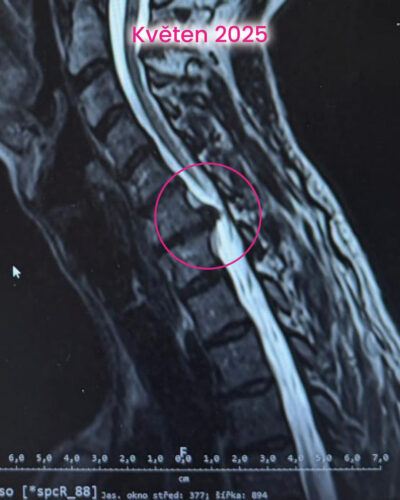

To je častý omyl. Cílem bylo snížit tlak na nerv, zklidnit nervový systém a vrátit tělu schopnost fungovat jako celek. Postupně jsme pracovaly s reflexními body, jemnou manuální terapií, stabilizací a změnou pohybových stereotypů. Velkou roli hrál i spánek, jeho nastavení a pravidelné cvičení několikrát denně v malých dávkách.

První změny přišly překvapivě rychle. Bolest začala ustupovat, brnění se objevovalo méně a spánek se postupně vracel. Přidaly jsme nordic walking pod vedením instruktora. V září byla klientka bez bolesti, spala bez přerušení a fungovala normálně v pohybu i běžném životě. V prosinci už si zase mohla nazout skialpové bot, skialpy a vyrazit na krátký trek.